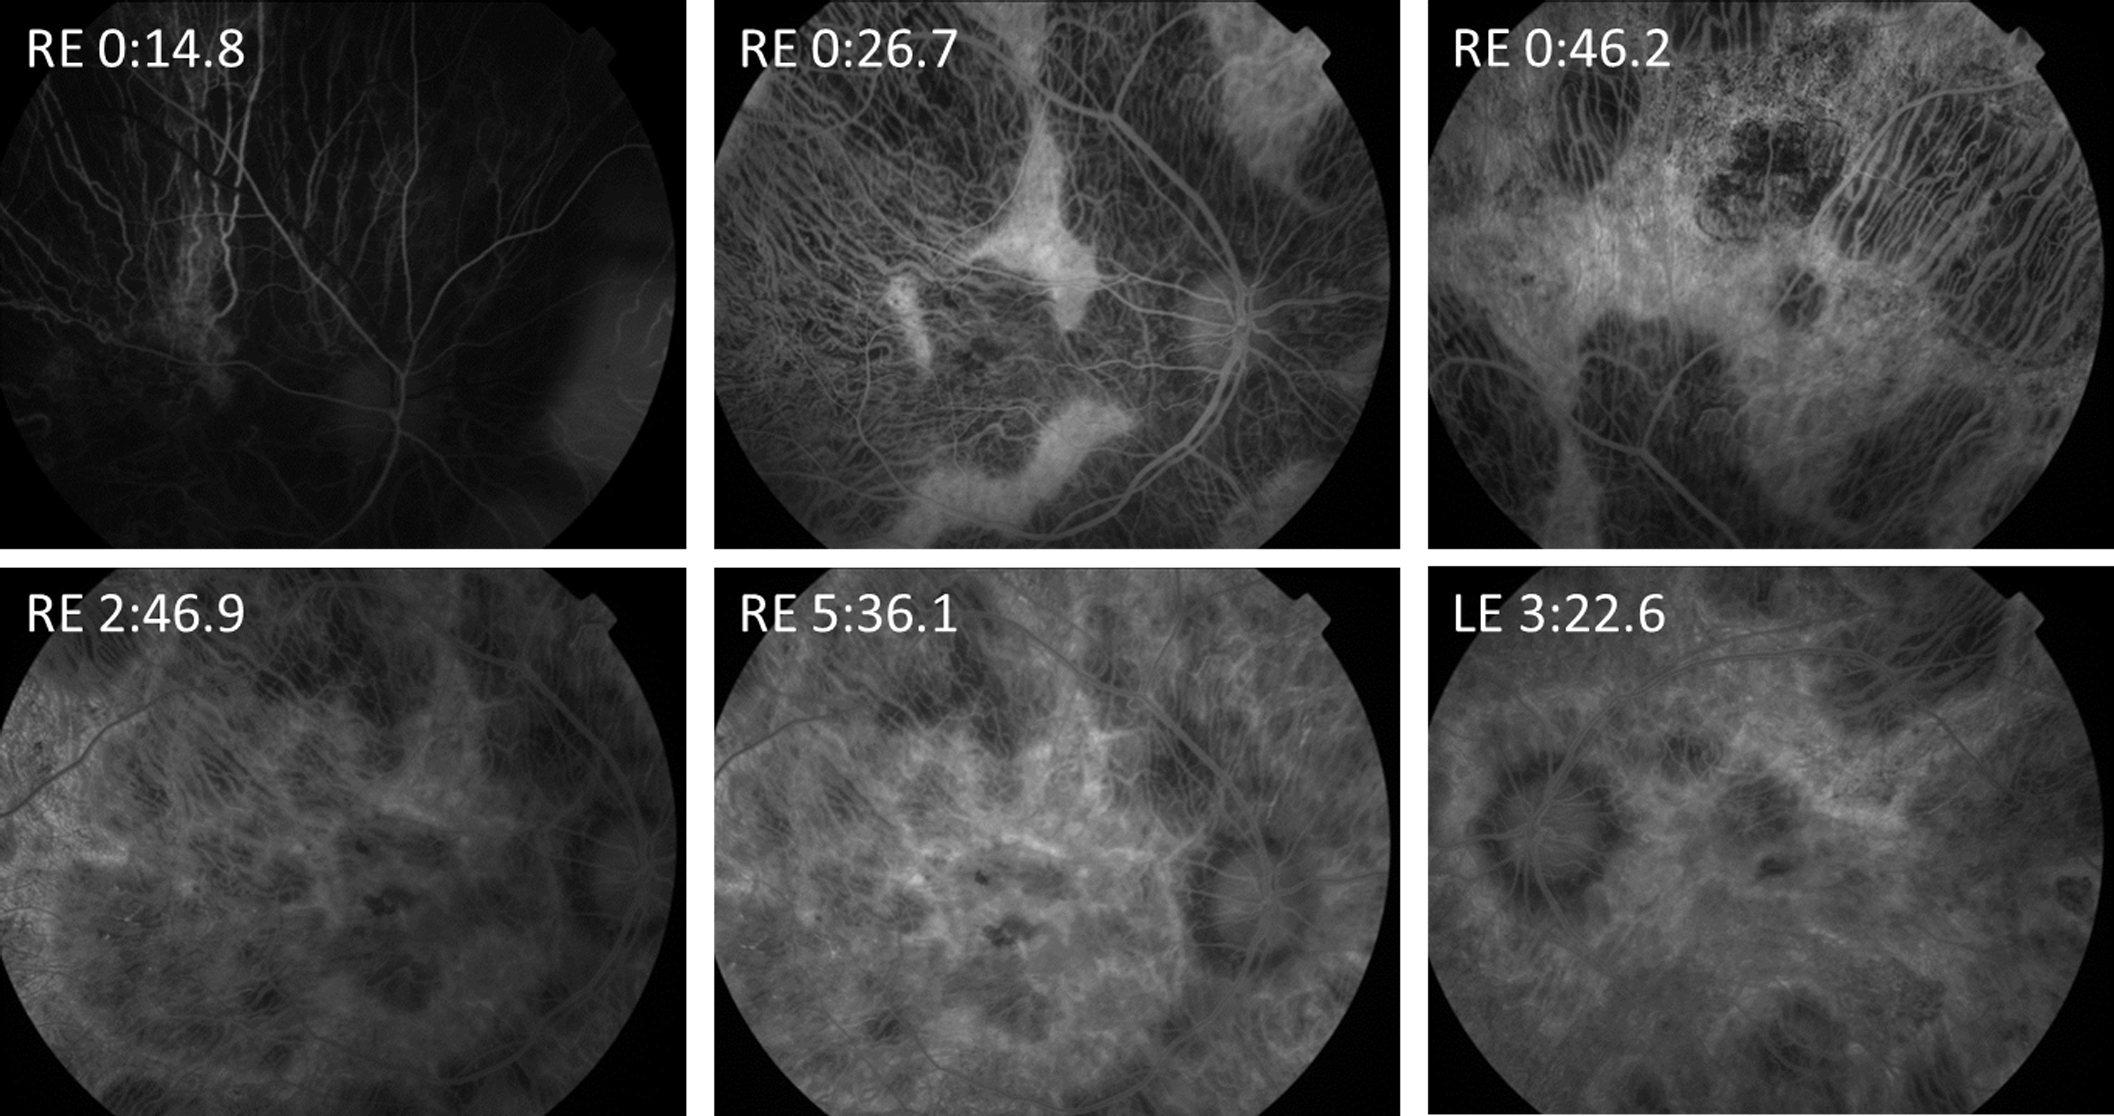

Figure 2 of Hull, Mol Vis 2016; 22:626-635.

Figure 2. Fundus fluorescein angiogram of patient 1.2 at increasing time points. Relative preservation of the retinal vasculature is apparent with the easily visible choroidal vasculature. RE, right eye. LE, left eye. Time in minutes.